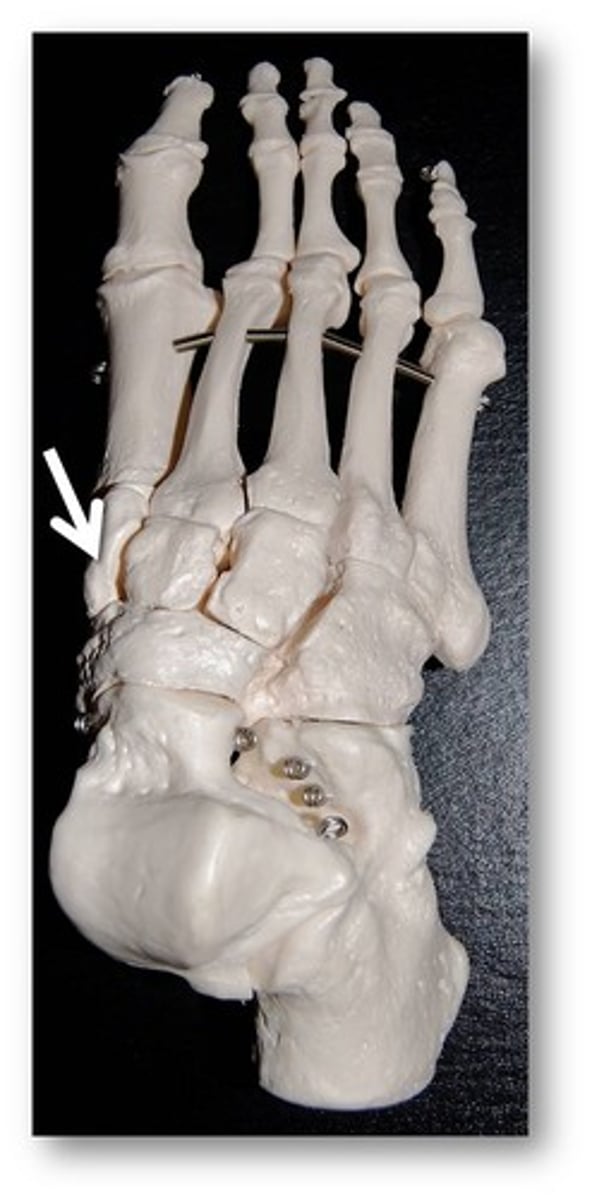

Calcaneus

Name this specific bone of the foot.

Calcaneus

Name this specific bone of the foot.

Cuboid

Name this specific bone of the foot.

Cuboid

Name this specific bone of the foot.

Medial cuneiform

Name this specific bone of the foot.

Metatarsals

Name these specific bones of the foot.

Phalanges

Name these specific bones of the foot.

Talus

Name this specific bone of the foot.

Tarsals

Name these specific bones of the foot.

Lateral cuneiform

Name this specific bone of the foot.

Lateral cuneiform

Name this specific bone of the foot.